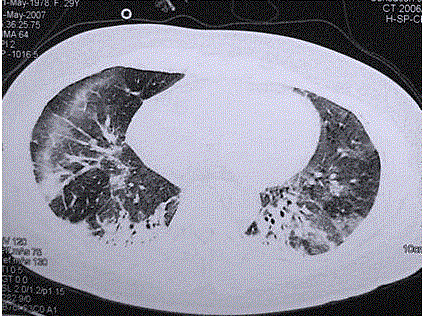

问题 患者女,29岁。间断干咳10年余,加重4个月,伴进行性呼吸困难1个月。病程中出现双手及双足非凹陷性肿胀、双侧膝关节及双侧肘关节对称性肿痛,面部出现细小红色丘疹。体检:T 36.5℃,P 88次/min,R 22次/min,BP 110/75 mmHg,SpO 93%(自然)。额部、前胸及后背散在红色小丘疹,双肺呼吸音增强,双肺中下肺野可闻及爆裂音,右肺明显。胸部CT 如图所示。 该患者最可能的诊断是(提示 患者无发热,血常规正常,痰培养阴性。)

选项 A.肺泡蛋白沉积症 B.军团菌肺炎 C.特发性间质性肺炎 D.结缔组织病肺受累 E.肺部恶性肿瘤 F.结节病 G.社区获得性肺炎

答案 D